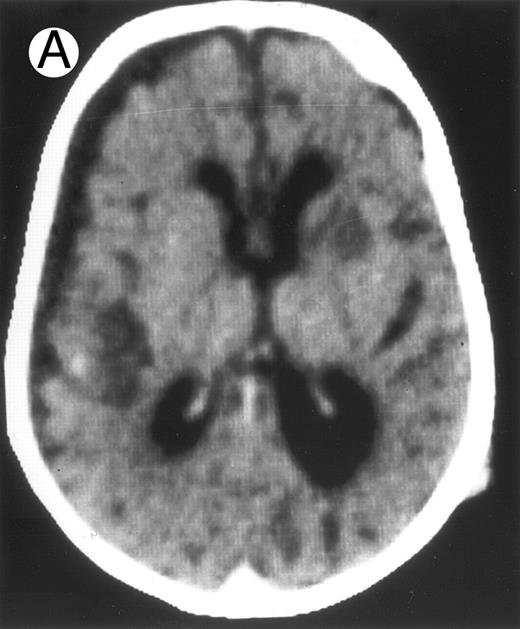

Among the nine children with initial neurological symptoms, seizures were the most frequent initial symptom in the youngest patients, whereas ataxia was found in the two oldest patients (46 and 58 months old, respectively) (Table 1). All nine patients had the same CSF abnormalities as patients with meningitis only. Eight of these nine patients had a neuroradiological study performed at the time of their first neurological symptoms (Table 1). The two most frequent lesions were focal necrosis with parenchymal volume loss and atrophy (Fig 2A and C) and white matter abnormalities (Fig 2B). Several small focal lesions with hypersignal at MR imaging that enhanced after administration of gadopentate dimeglumine (or contrast on CT scan) were also observed in two cases.

Three different aspects of brain imaging in HLH patients. (A) CT scan of a 3-month-old baby showing a large subdural effusion, several necrotic areas and hypodensities of the white matter. (B) Brain magnetic resonance of a 14-month-old boy showing large confluent areas of hypersignal in T2-weighted images. (C) Large symmetrical necrotic areas of cerebellar white matter in a 41/2-year-old girl (MRI).